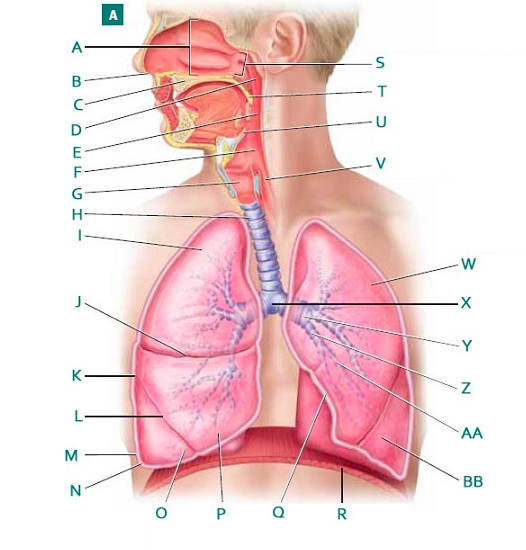

Alveolus/alveoli

Bronchioles

C-Rings (=tracheal cartilage)

Epiglottis

Larynx

Left/right primary bronchus/bronchi

Naso/oro/laryngo-phraynx

I

H

G

Secondary bronchi

Upper/middle/lower lobe (of lung)